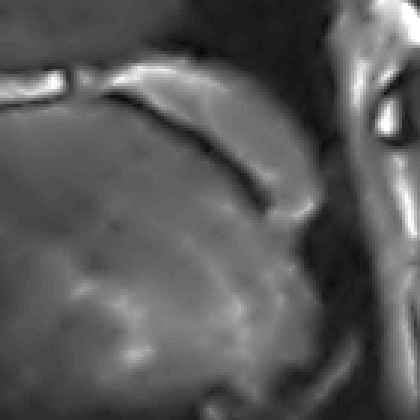

We display the noisy image and the reconstructed images from these three denoising methods in Fig. 8 111 Image retrieved from http://radiopaedia.org/ by Frank Gaillard.. To better understand the performance, we zoom in the selected part of the image and display them in Fig. 9.

We observe that the anisotropic TV suffers from the staircase artifact due to the fact that the TV is local operator. On the other hand, the reconstruction with TFV regularity has blurry effect on the edges. This is not surprising because the TFV is a non-local method and it is less edge sensitive than TV. Instead, the TV-TFV regularity avoids such artifacts and has a better reconstruction of both the edges and the overall image.

We also present the numerical results of different performance measurements in Table 3. The TV-TFV regularity shows better results in such measurements as well.

We point out that the noisy image in Fig. 10 is obtained directly by inverse Fourier transform and we can see that the noise level is quite high in this case. Both the PCM-TV and the PCM-TV-TFV are able to produce more reasonable visual results. To see a deep comparison, we zoom in the red square part of Fig. 10 and present the approximation errors in Fig. 11.